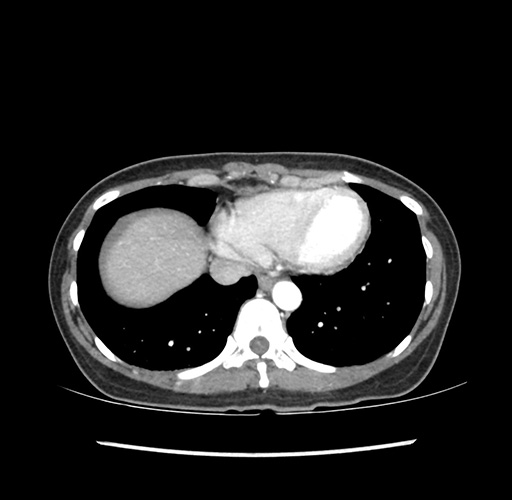

Imaging Analysis

Look through the patient's CT scan to identify any areas of concern for the necessary procedure.

Based on your CT findings, which issue(s) would give reason for "planned slowing down moment(s)" in this case?